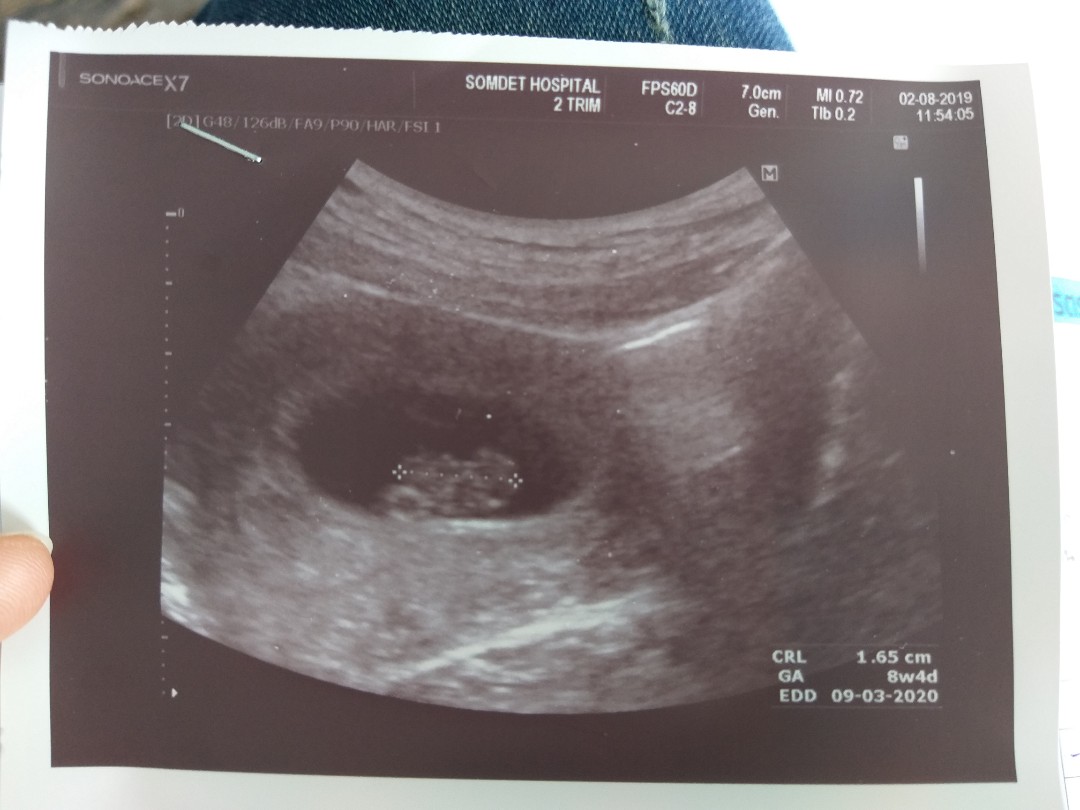

7w+ค่ะ เจ้าจิ๋ว

10w4d ตอนนี้20w4d